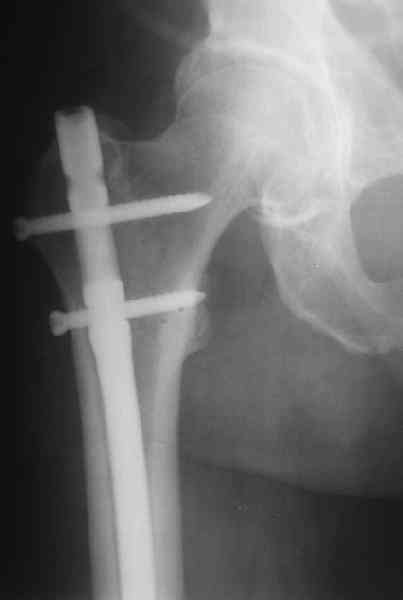

На операцию пошли, имея в возможных планах практически все прозвучавшие предложения - и про пластину, и про аппаратную коррекцию. Была даже несколько экстравагантная идея закрыто убрать винты из диафизарной части пластины, наложить аппарат, постепенно восстановить ось и длину, после чего вновь ввести винты в пластину, подложив шайбы между пластиной и костью.

Удалили ластину без проблем. Выявилась значительная подвижность. В этих условиях сразу пропала мотивация к постепенной коррекции аппаратом. Попробовал восстановить длину, введя между отломками spreader. Отчасти удалось. Тогда защили рану, наложили спицевой дистрактор (2 спицы в дистальный отдел и 1 вверху). после этого был убран и спонгиозный винт. И сделали антгерадное штифтование, как говорится, "по принятой в

клинике методике".

Дополнительные доступы для введения гвоздя и проксимальных винтов понадобились, но они маленькие, по 1 см. Нижние винты ввели прямо между швами. Суставы дополнительно не травмировали, и даже ввели гвоздь не через f. piriformis, а через большой вертел.

Длину восстановили, возможно, даже с изьбытком, ну да динамизируем пораньше. Введенные в овальное отверстие дистальые винты имеют угловую стабильность. Снимки приложены. Заранее спасибо за критику и комментарии.